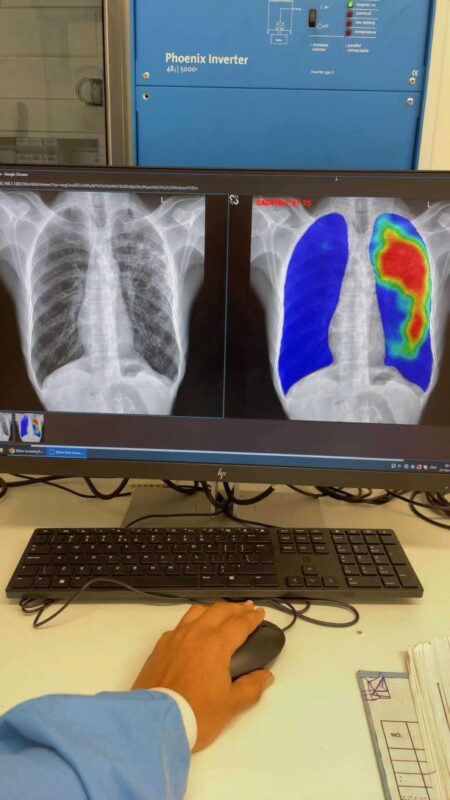

A radiographer reviewing CAD4TB chest X-ray results on a monitor, with AI-generated heat maps highlighting lung abnormalities, inside a mobile clinic in Ghana.

A radiographer reviewing a CAD4TB chest X-ray analysis on a monitor, showing the original image alongside an AI-generated heat map highlighting lung abnormalities, inside a mobile clinic in Ghana.